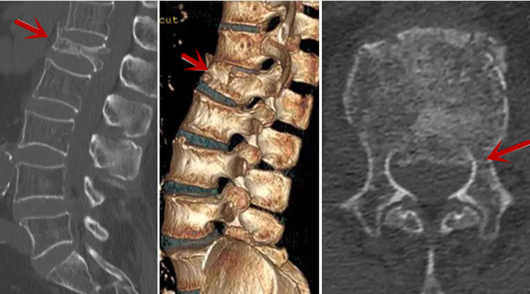

利器二:CT

CT利用X射線對人體檢查部位通過電腦切成若干層掃描,然后把每層的圖像都能顯示出來。CT相對于X光片具有更高的密度分辨力,可直接顯示X線片無法顯示的病變,觀察腰椎有無微小的骨折、骨質(zhì)有無破壞等骨質(zhì)情況、以及腰椎間盤突出、腰椎神經(jīng)根、椎管、椎間小關(guān)節(jié)的情況等。同時還可以通過后處理,重建腰椎矢狀位或冠狀位圖像,形成腰椎的3D圖像,更直觀地觀察病變部位,對腰椎手術(shù)風(fēng)險具有提示作用,對手術(shù)方式的選擇具有指導(dǎo)意義,但是對神經(jīng)、脊髓損傷程度的顯示不如MRI,軟組織的分辨率仍有一定限制,對椎管內(nèi)病變顯示欠佳,且有一定的輻射。

從左向右依次為CT矢狀位重建圖像、三維重建圖像、軸位掃描圖像,箭頭提示腰1椎體爆裂性骨折